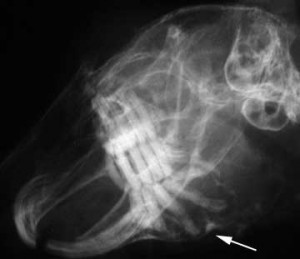

Uši (Otitis externa)

Při silném znečistění může vzniknout zánět vnějšího zvukovodu.

Symptomy: Zvířata si škrábou uši nebo otírají

hlavu o podlahu. V těžkých případech drží hlavu nakřivo. Ze zvukovodu

vytéká nahnědlý hnis, který může způsobit zánět okolní kůže. Díky výtoku můžeme vyloučit zánět středního ucha.

Léčba: Postižený zvukovod je třeba pořádně vyčistit smotkem vaty.

V žádném případe se nesmí používat přípravky obsahující alkohol,

které Ize koupit jako takzvané »léky na čistění uší«, aby nepoškodily

již tak dost narušený epitel zvukovodu. Po důkladném vyčištění zvukovodu

se pomocí smotku vaty aplikuje zinková mast s rybím tukem Zincojecol. Veterinář provede rentgen a nasadí léky.

Pokud si činčilka škrábe uši, musí se vnitřek ucha lehce vyčistit

Na rentgenu vidíme na pravé straně tmavé místo se zánětem zvukovodu